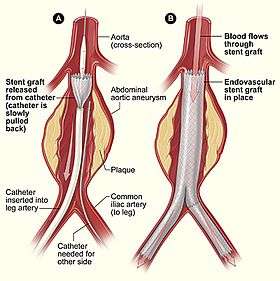

Minimally invasive procedures (also known as minimally invasive surgeries) have been enabled by the advance of various medical technologies. Surgery by definition is invasive and many operations requiring incisions of some size, are referred to as open surgery. Incisions made can sometimes leave large wounds that are painful and take a long time to heal. Minimally invasive surgery refers to surgical techniques that limit the size of incisions needed and so lessens wound healing time, associated pain and risk of infection. An endovascular aneurysm repair as an example of minimally invasive surgery is much less invasive in that it involves much smaller incisions, than the corresponding open surgery procedure of open aortic surgery. This minimally invasive surgery became the most common method of repairing abdominal aortic aneurysms in 2003 in the United States.[1]